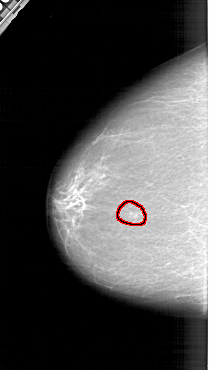

A_1308_1.LEFT_MLO

FILE: A_1308_1.LEFT_MLO.OVERLAY

TOTAL_ABNORMALITIES 1

ABNORMALITY 1

LESION_TYPE MASS SHAPE LOBULATED MARGINS ILL_DEFINED

ASSESSMENT 4

SUBTLETY 3

PATHOLOGY BENIGN

TOTAL_OUTLINES 1

BOUNDARY